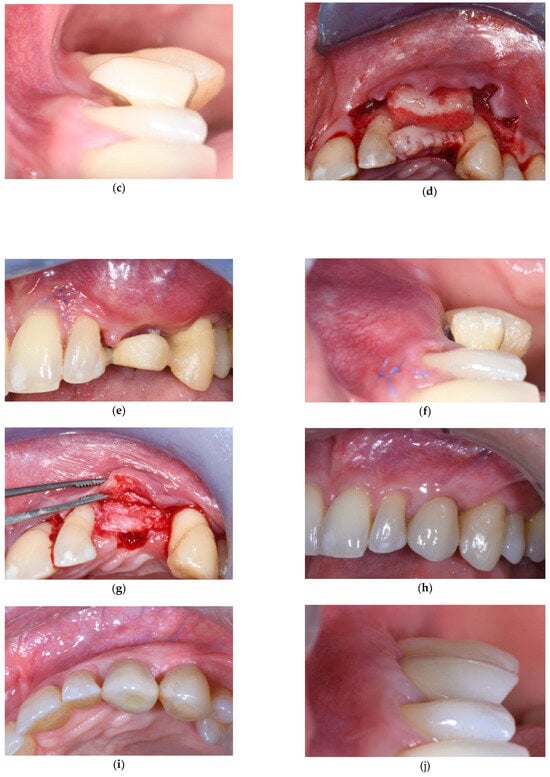

2. Connective Tissue Substitutes: Properties and Applications

3.1. Soft Tissue Augmentation Before Implant Installation

3.2. Soft Tissue Augmentation During Implant Installation

3.3. Soft Tissue Augmentation After Implant Installation